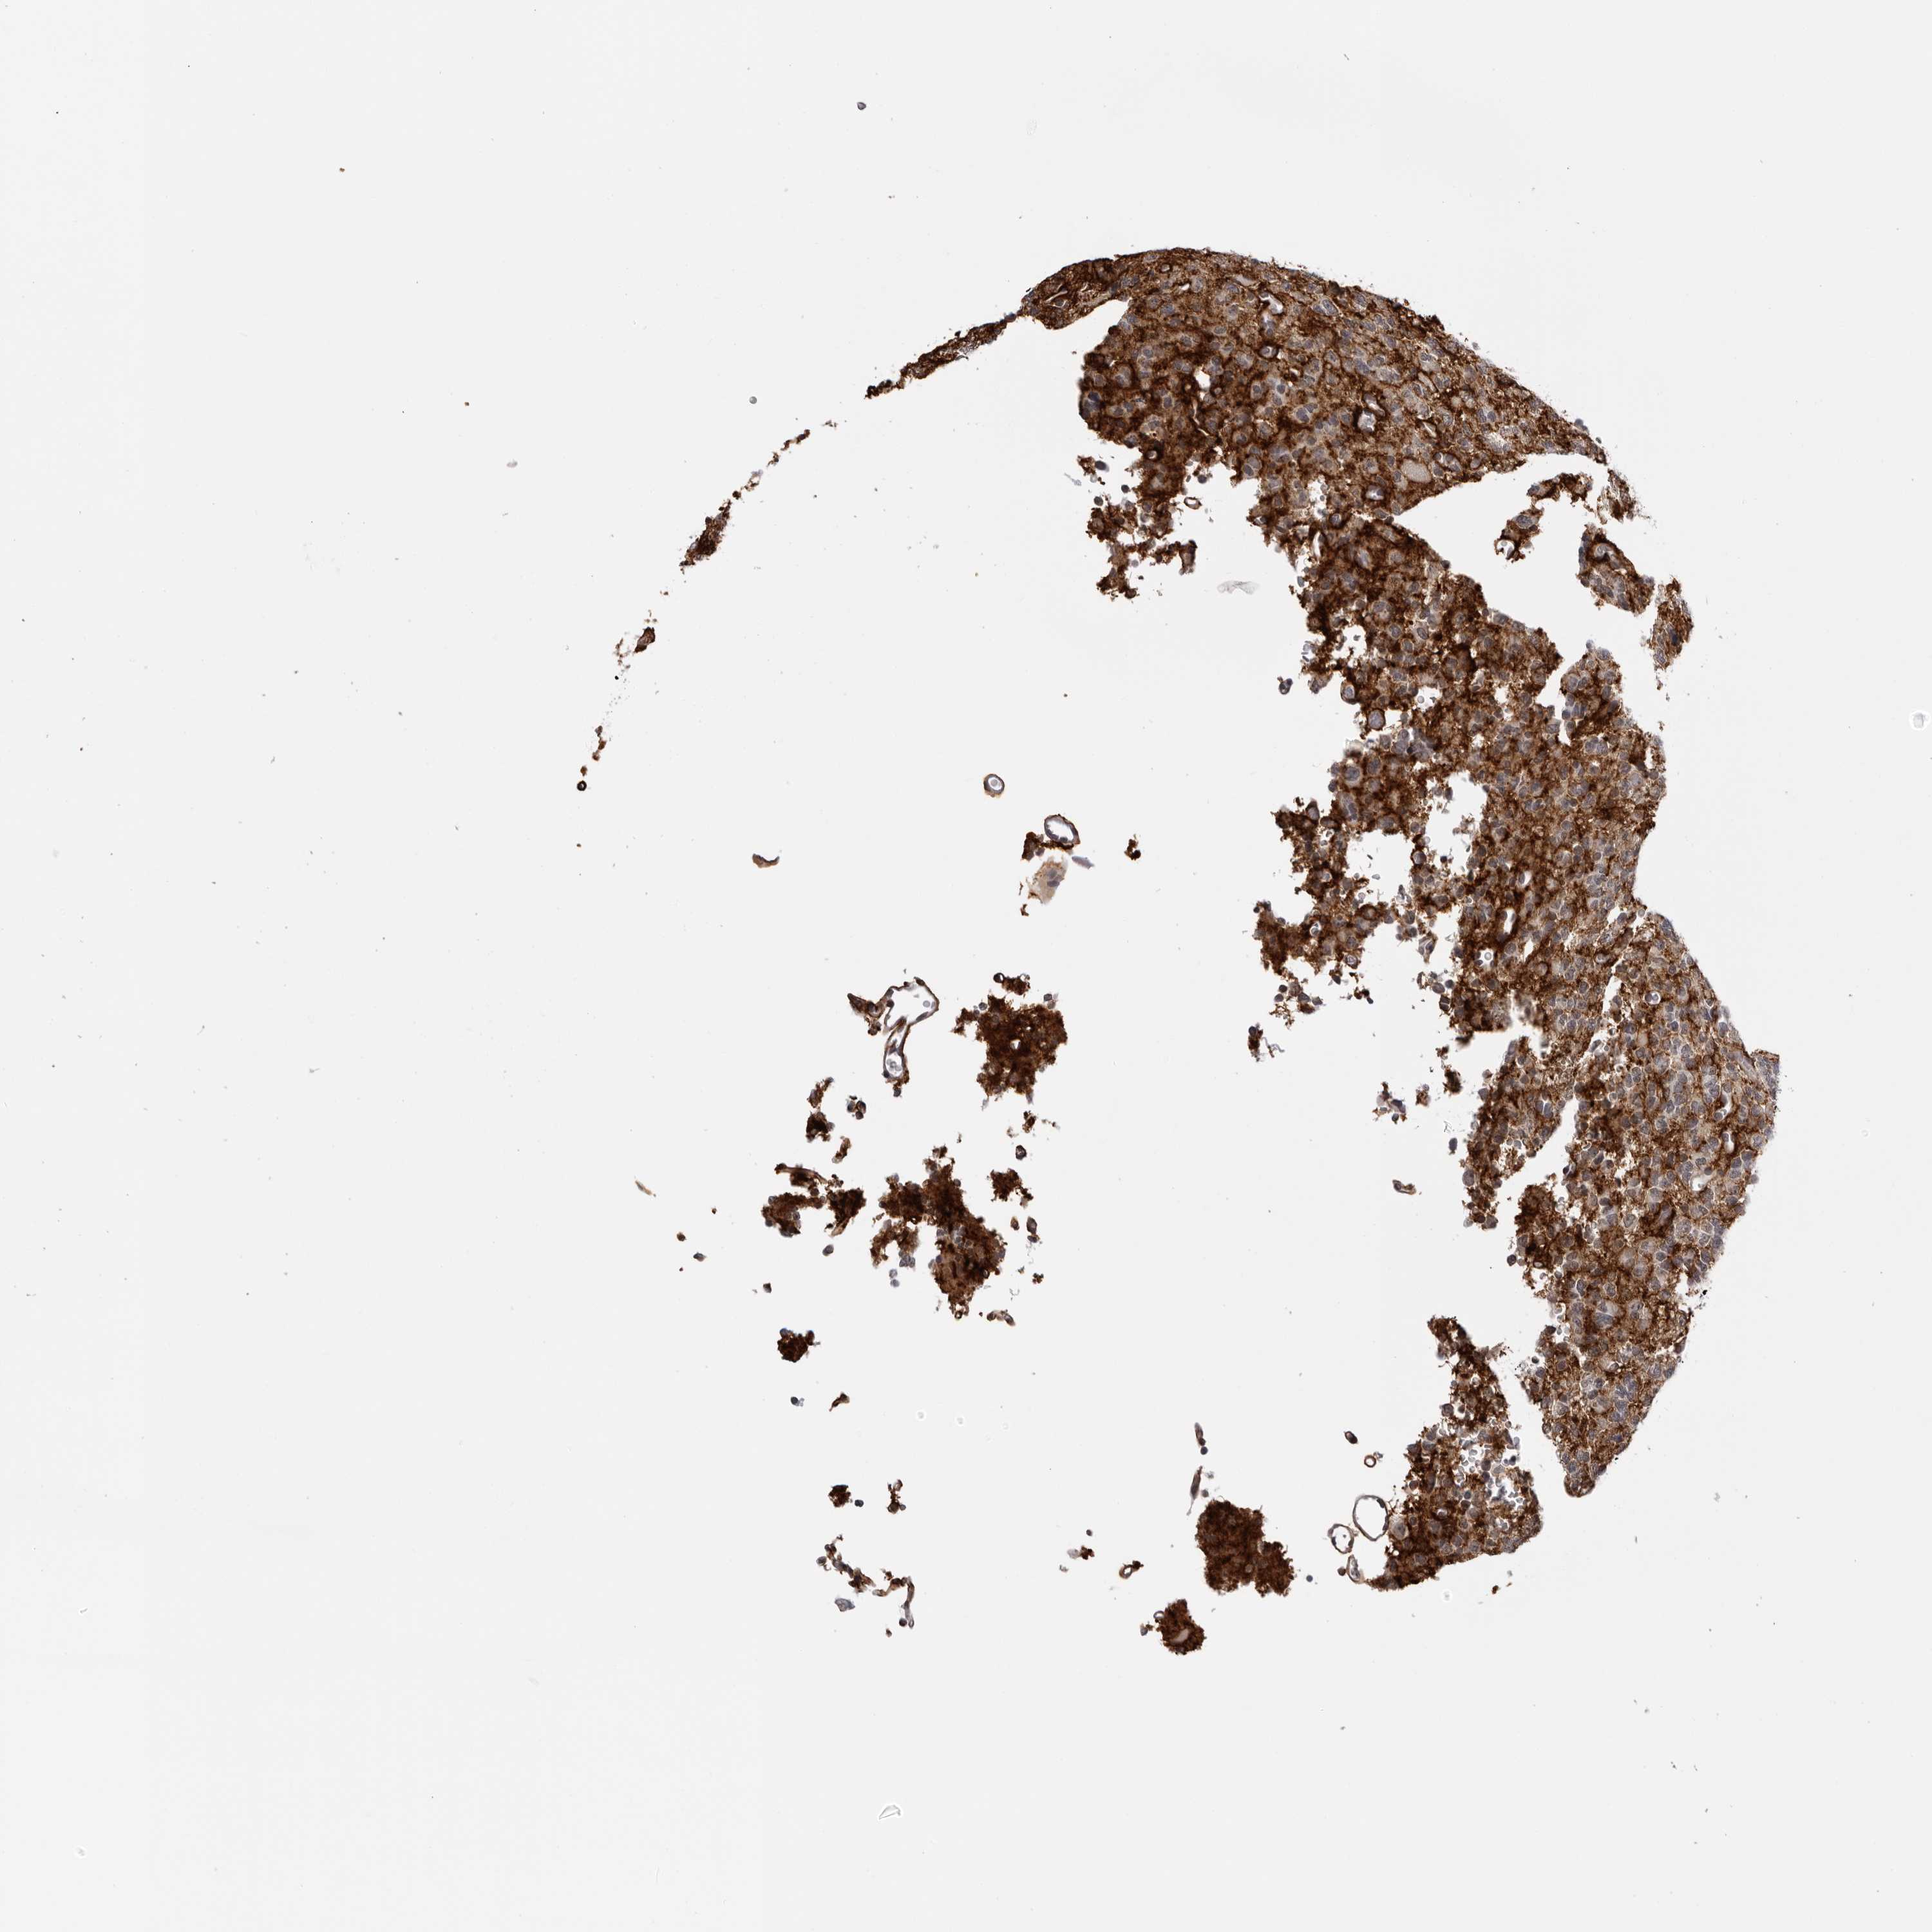

GLIOMA - Protein expressioni

A mouse-over function shows sample information and annotation data. Click on an image to view it in a full screen mode. Samples can be filtered based on level of antibody staining by selecting one or several of the following categories: high, medium, low and not detected. The assay and annotation is described here.

Note that samples used for immunohistochemistry by the Human Protein Atlas do not correspond to samples in the TCGA dataset.

Antibody stainingi

Antibody staining in the annotated cell types in the current human tissue is reported as not detected, low, medium, or high, based on conventional immunohistochemistry profiling in selected tissues. This score is based on the combination of the staining intensity and fraction of stained cells.

Each image is clickable and will lead to virtual microscopy that enables deeper exploration of all samples and also displays staining intensity scores, fraction scores and subcellular localization as well as patient and tissue information for each sample.

Antibody HPA028411

Staining

High

Medium

Low

Not detected

Intensity

Strong

Moderate

Weak

Negative

Quantity

>75%

75%-25%

<25%

None

Location

Nuclear

Cytoplasmic/membranous

Cytoplasmic/membranous,nuclear

Glioma, malignant, High grade

Glioma, malignant, Low grade